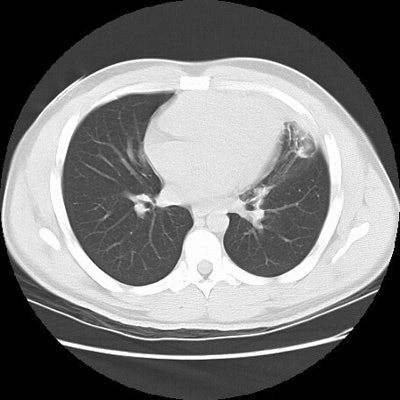

Rounded atelectasis in a patient with prior granulomatous infection

Asbestos related pleural disease is not the only cause of rounded atelectasis. The patient shown in the images below had a prior granulomatous infection with densely calcified left hilar adenopathy. There is extensive plerual thickening seen along the left anterior pleural surface. Rounded consolidated lung can be seen to abut this area of pleural thickening. Lung markings "swirl" into the area of abnormality. There is shift of the mediastinal structures to the left consistent with volume loss.